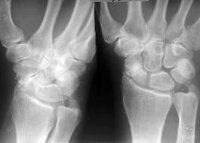

Рентгенография лучезапястного сустава

Рентгенография лучезапястного сустава. Рентгенологическое исследование, показанием к которому в травматологии является подозрение на переломы и переломы дистальной части лучевой и локтевой костей, переломы, вывихи и переломы костей запястья. В других областях медицины метод используется при нарушениях развития, дегенеративно-дистрофических изменениях, гнойных и опухолевых процессах. Процедура не требует подготовки, ее можно проводить амбулаторно или в больнице. В период беременности и в детском возрасте рекомендуется заменить рентгенографию лучезапястного сустава альтернативными методами из-за высокой радиационной нагрузки.

Рентгенограммы запястья в травматологии обозначают подозрение на перелом лучевой кости в типичном месте, перелом Галеацци (перелом дистального радиуса в сочетании с вывихом головки локтевой кости), стилоид перелома и лучевой кости локтевой кости, переломовичихи, искажения и переломы перелома кости запястья. Показаниями к обучению в ортопедии являются артрозы и пороки развития. В ревматологии методика используется для оценки состояния суставов при ревматоидном артрите и ряде других заболеваний. В гнойной хирургии процедура применяется при артрите лучезапястного сустава, в онкологии, при подозрении на доброкачественные и злокачественные новообразования в этой области.